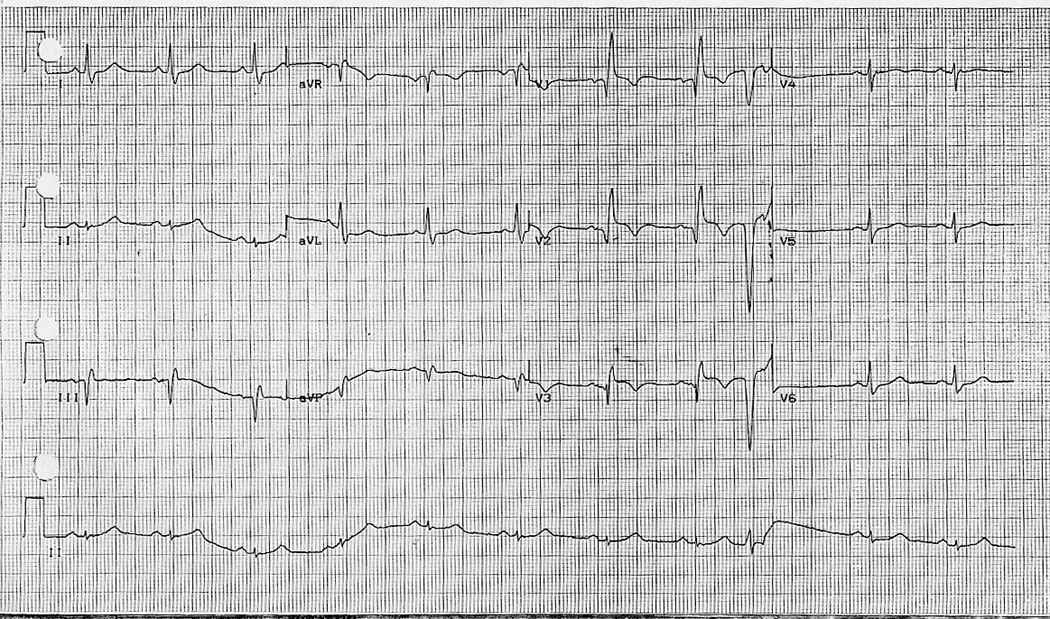

EKG 26